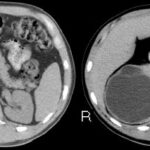

Fase nefrográfica o portal

Se logra a partir de los 80 a 180 segundos posteriores a la inyección del contraste; el medio de contraste se encuentra en los túbulos colectores y asa de Henle durante esta fase y su utilidad se basa en el aumento homogéneo del parénquima renal, lo que permite una mejor delimitación de la masa renal.

Durante esta fase se presenta el mayor realce de los tumores sólidos, por lo que se logra una mejor caracterización de las masas indeterminadas. En un estudio sobre la caracterización de las masas renales menores a 3 cm se concluyó que durante las exploraciones en fase nefrográfica se permitió una mayor detección de lesiones y una mejor caracterización de las masas renales pequeñas que en las exploraciones de fase corticomedular 3-5 (Fig. 3).